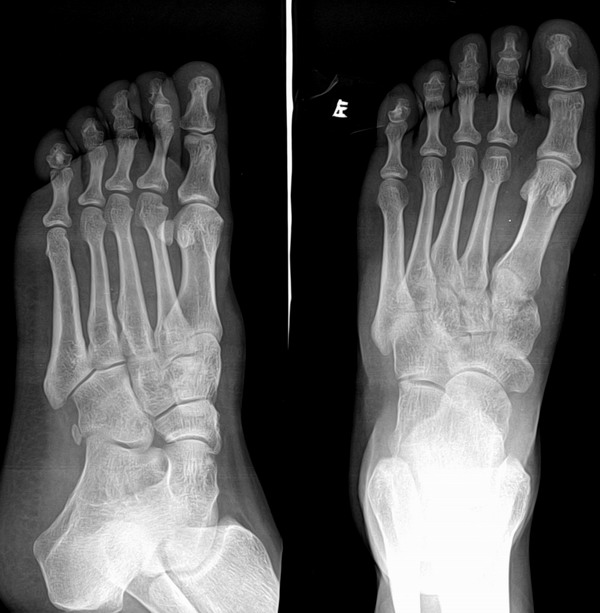

大家看看是正常还是异常?

病人的受伤部位不在这里,只是想让大家看看!

正常骨岛吧!

正常骨岛

未见异常。

正常,趾骨表现为正常,不是骨岛.